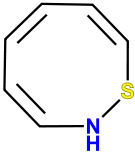

Benzomorphans

Structures

| Benzomorphans | ||||

Thiazocine Thiazocine |